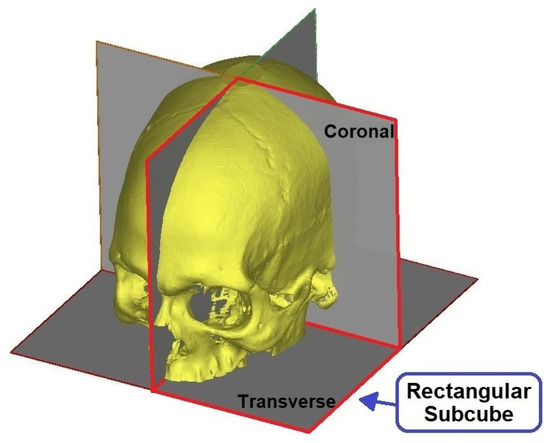

To reduce the computational and processing time, these images were reduced to 128 × 128 using the nearest neighbor interpolation method. Additionally, the volumetric image was divided into four rectangular sub-cubes and only one-quarter of the whole image space was used to predict the angles as shown in Figure 6. As this step aims to identify the coronal and transverse angles in symmetrical skulls, these steps do not affect the output image. Figure 7 summarizes this process.

Figure 6.

Volumetric image divided into rectangular subcubes and the selected one-quarter subcube.